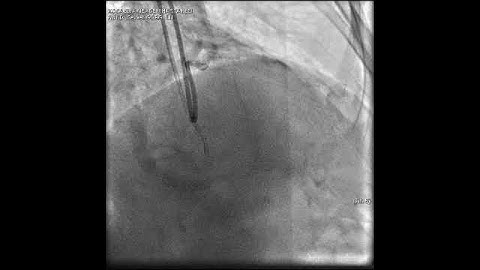

Aortic dissection and radial rupture during retrograde CTO PCI: Management of complications VİDEO 15